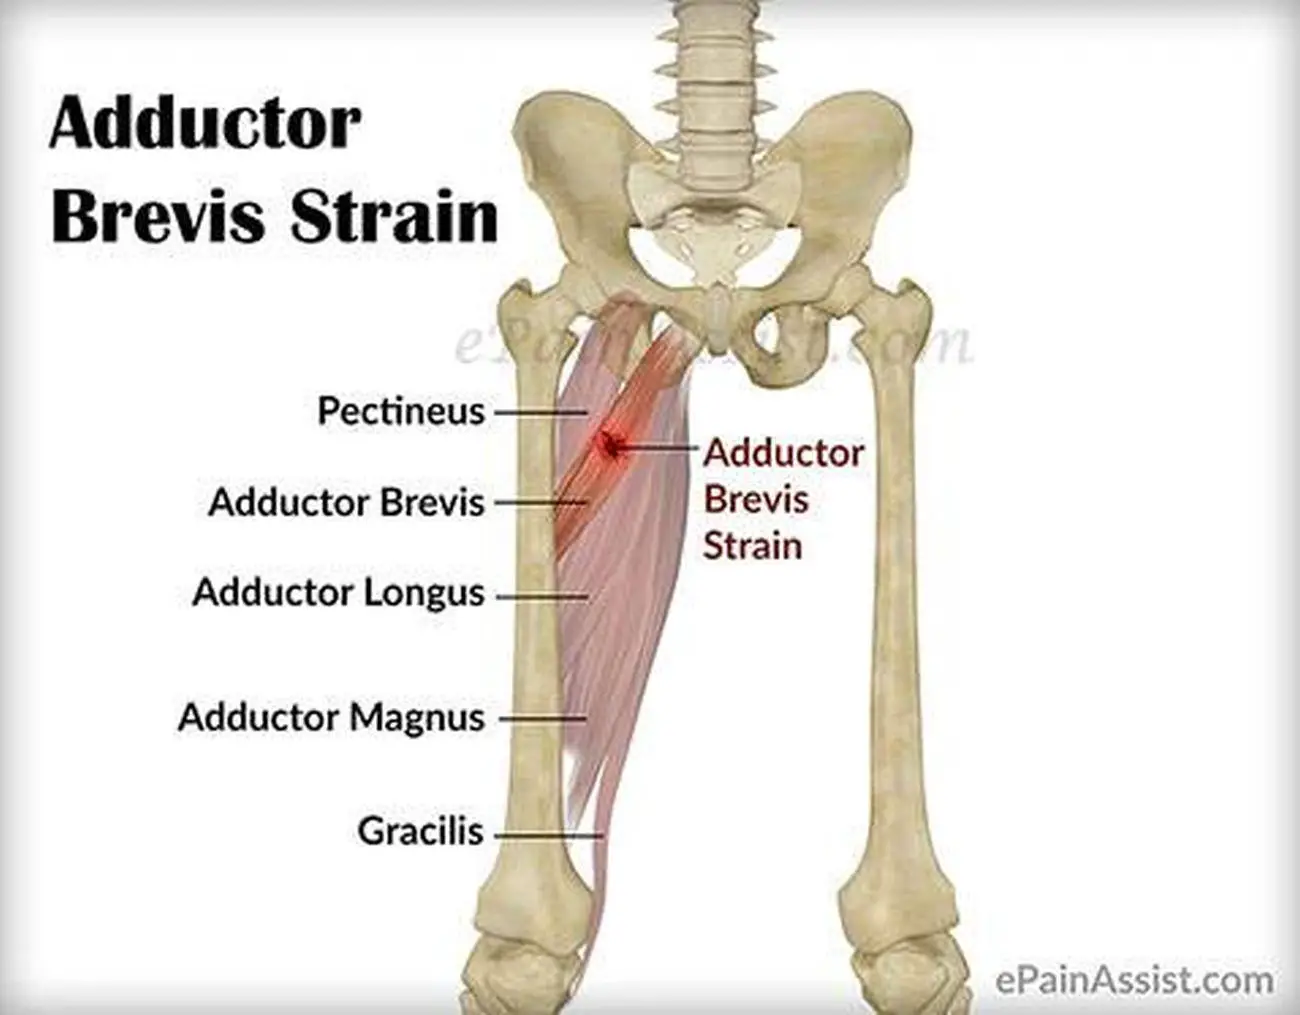

Анатомия и Функции Мышцы Adductor Magnus